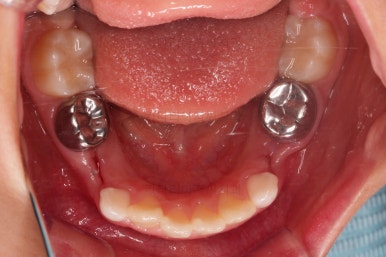

치료가 도저히 불가능한 유치는 발치를 하고, 대신 영구치가 나오기까지 매우 오래 걸릴 것으로 예상되어서 주위 치아들의 위치가 잘 유지되라고 공간유지장치를 해줬어요.

전문 용어로 band&loop라고 하는 이렇게 해줘야 추후에 또 다른 더 큰 문제가 생기지 않는답니다.

보호자분 : "공간유지장치 부분으로 치아가 보여요!"

키다리 : "오~ 잘됐네요. 장치는 제거해도 됩니다."

장치 제거는 어떤 치과에서도 간단히 할 수 있기 때문에 장치를 제거해도 되겠다는 조언을 드렸고 다행히 유지장치 덕분에 영구치가 제대로 잘 나올 수 있었어요.